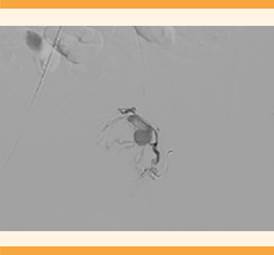

A su llegada al hospital de tercer nivel, la paciente se encontró estable y con sangrado en menor cantidad, pero persistente. Fue valorada por el radiólogo. Ante la sospecha de una malformación vascular se decidió proceder a la arteriografía pélvica en la que se objetivó una formación sacular, dependiente de la arteria hipogástrica izquierda, compatible con un pseudoaneurisma (Figuras 3 y 4) que justificaba la clínica de la paciente. Por ello, se decidió practicarle un cateterismo con embolización selectiva de la rama aferente del pseudoaneurisma, que concluyó sin contratiempos y se comprobó la ausencia de flujo a la formación aneurismática posterior a la embolización. Figura 5